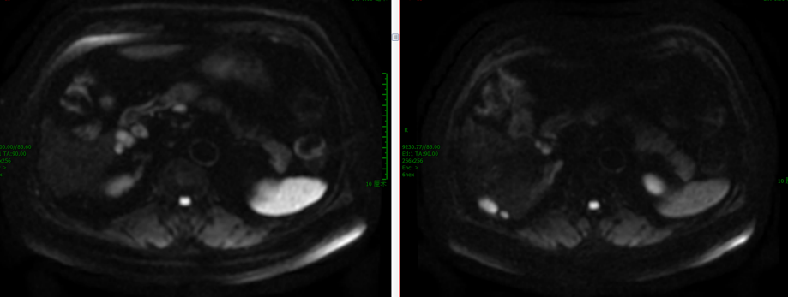

【TAS-102+呋喹替尼】2021-6-11 上腹部MRI提示“直肠CA根治术+肝转移瘤切除术+胆囊切除术”后改变,肝右叶肿瘤介入术后,肝右叶部分病灶较前(2020-12-2)范围缩小,部分病灶较前为新增,肝门区及后腹膜处多发肿大淋巴结,肝右叶见结节、斑片灶,较大者直径约35mm;胸部CT提示右肺上叶斜裂胸膜下结节,较前(2021-2-10)病灶内小空泡消失。两肺多发小斑点灶及小结节,较前部分有所减小,期间有肿瘤标志物进行性升高。

2021-7-8行五线7疗程呋喹替尼+TAS-102治疗,期间疗效评估SD(缩小)。

继续【TAS-102+呋喹替尼】口服。

2021-12-7 胸部CT:右肺上叶斜裂胸膜下结节,较前缩小。

腹部MRI:肝右叶部分凝固性坏死边缘伴火星,后腹膜肿大淋巴结。